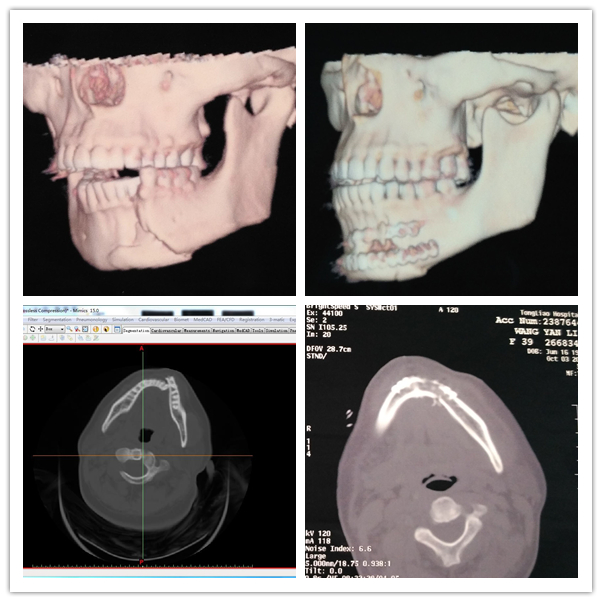

在此期间,通过仔细了解病史,发现患者有鼻部外伤病史,不确定能否顺利经鼻腔气管插管麻醉,必要时需经口腔气管插管麻醉后行颌下入路留置气管导管,以便术中确认患者咬合关系。通过数字化软件重建患者颌骨骨折断端后发现下颌骨颊舌侧均有多个碎骨片,增加了手术的难度。

经过白高山大夫一周的精心治疗,患者全身状况具备手术条件,决定即刻进行手术。手术按原计划顺利展开。在做好充分准备后,患者被接入手术间,由西院口腔科靳勇医生主刀、白永刚主任亲自主持麻醉,患者双侧鼻腔狭窄,无法经鼻腔气管插管麻醉,经口腔气管插管麻醉后行颌下入路留置气管导管。经历了两个小时的辛苦奋战终于成功完成手术。